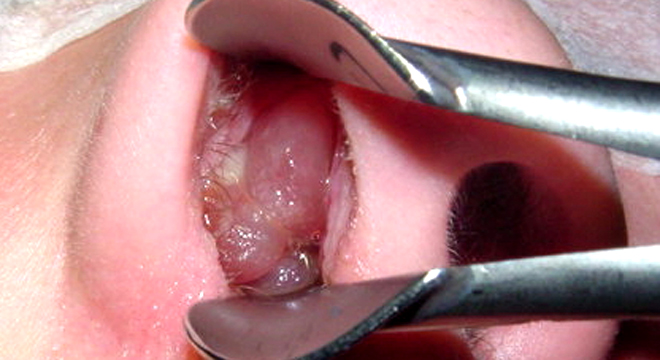

Grosse Nasenpolypen, die zunehmend Beschwerden machen, müssen operativ entfernt werden. Dabei ist heute die schonende Knopfloch-Chirurgie das Standardprozedere.